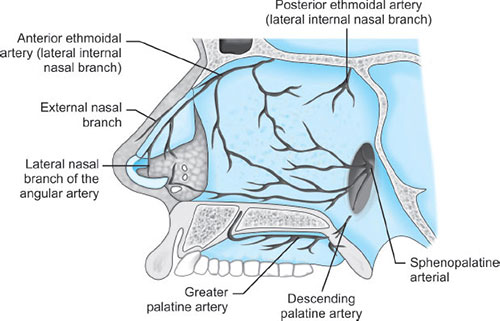

Blood Supply (Fig. 3)

- Ethmoid branches of the ophthalmic artery

- Sphenopalatine and greater palatine branches of the maxillary artery

- Superior labial and lateral nasal branches of the facial artery.

Kiesselbach's plexus, where these vessels anastomose, is situated in Little's area on the anterior-inferior portion of the nasal septum—a source of significant epistaxis.